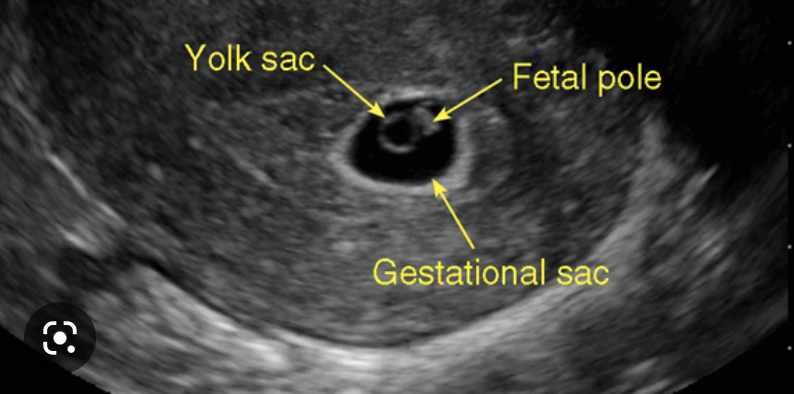

What is an anembryonic pregnancy?

a gestational sac is present but it contains no embryo

How is a miscarriage diagnosed?

transvaginal USS

What 3 features are looked for on transvaginal US to determine the viability of a pregnancy?

• mean gestational sac diameter

• foetal pole + crown-rump length

• fetal heartbeat

these appear sequentially so as each feature develops, the previous becomes less relevant in determining viability of a pregnancy

How is an anembryonic pregnancy diagnosed on transvaginal USS?

• a fetal pole is expected once mean gestational sac diameter is 25mm or more

• if the MGSD is >25mm and there is no fetal pole, scan is repeated after 1 week

• if the fetal pole is still not present, this is an anembryonic pregnancy